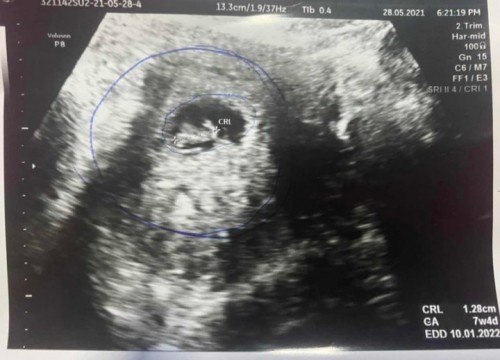

ภาพในใบซาวด์ใช่ตัวน้องรึป่าวคะ เพราะตอนไปซาวด์คุณหมอแจ้งว่าหาตัวน้องไม่เจอ อาจเพราะอายุครรภ์ยังน้อยเกินไป (ตอนที่ไปหาอายุครรภ์ 8w5d) แต่พอคุณหมอกดไปกดมาก็มาเจอตามในภาพ แต่คุณหมอพูดว่าก็ไม่รู้ว่าเป็นอะไร มองไม่รู้ เพราะไม่เห็นสัญญานหัวใจของน้องเต้น ก็ให้รออีก 2 อาทิตย์แล้วมาซาวด์ใหม่ แต่ในระหว่าง 2 อาทิตย์หากมีอาการปวดท้องหรือเลือดออกให้ไปรพ.ได้เลย เพราะครรภ์ไม่สมบูรณ์ และในใบซาวด์ระบุอายุครรภ์ 7w4d ไม่ตรงกับของแม่ แต่ตอนนี้ผ่านมาได้ 7 วันแล้ว แม่ก็ไม่ได้อาการตามที่คุณหมอเกริ่นไว้แต่อย่างใด เลยอยากให้แม่ๆช่วยดูหน่อยค่ะ ว่าในภาพนั่นคือตัวน้องใช่หรือป่าวคะ เพราะคำพูดของหมอทำให้แม่ไม่สบายใจเลยค่ะ #ขอบคุณล่วงหน้านะคะ